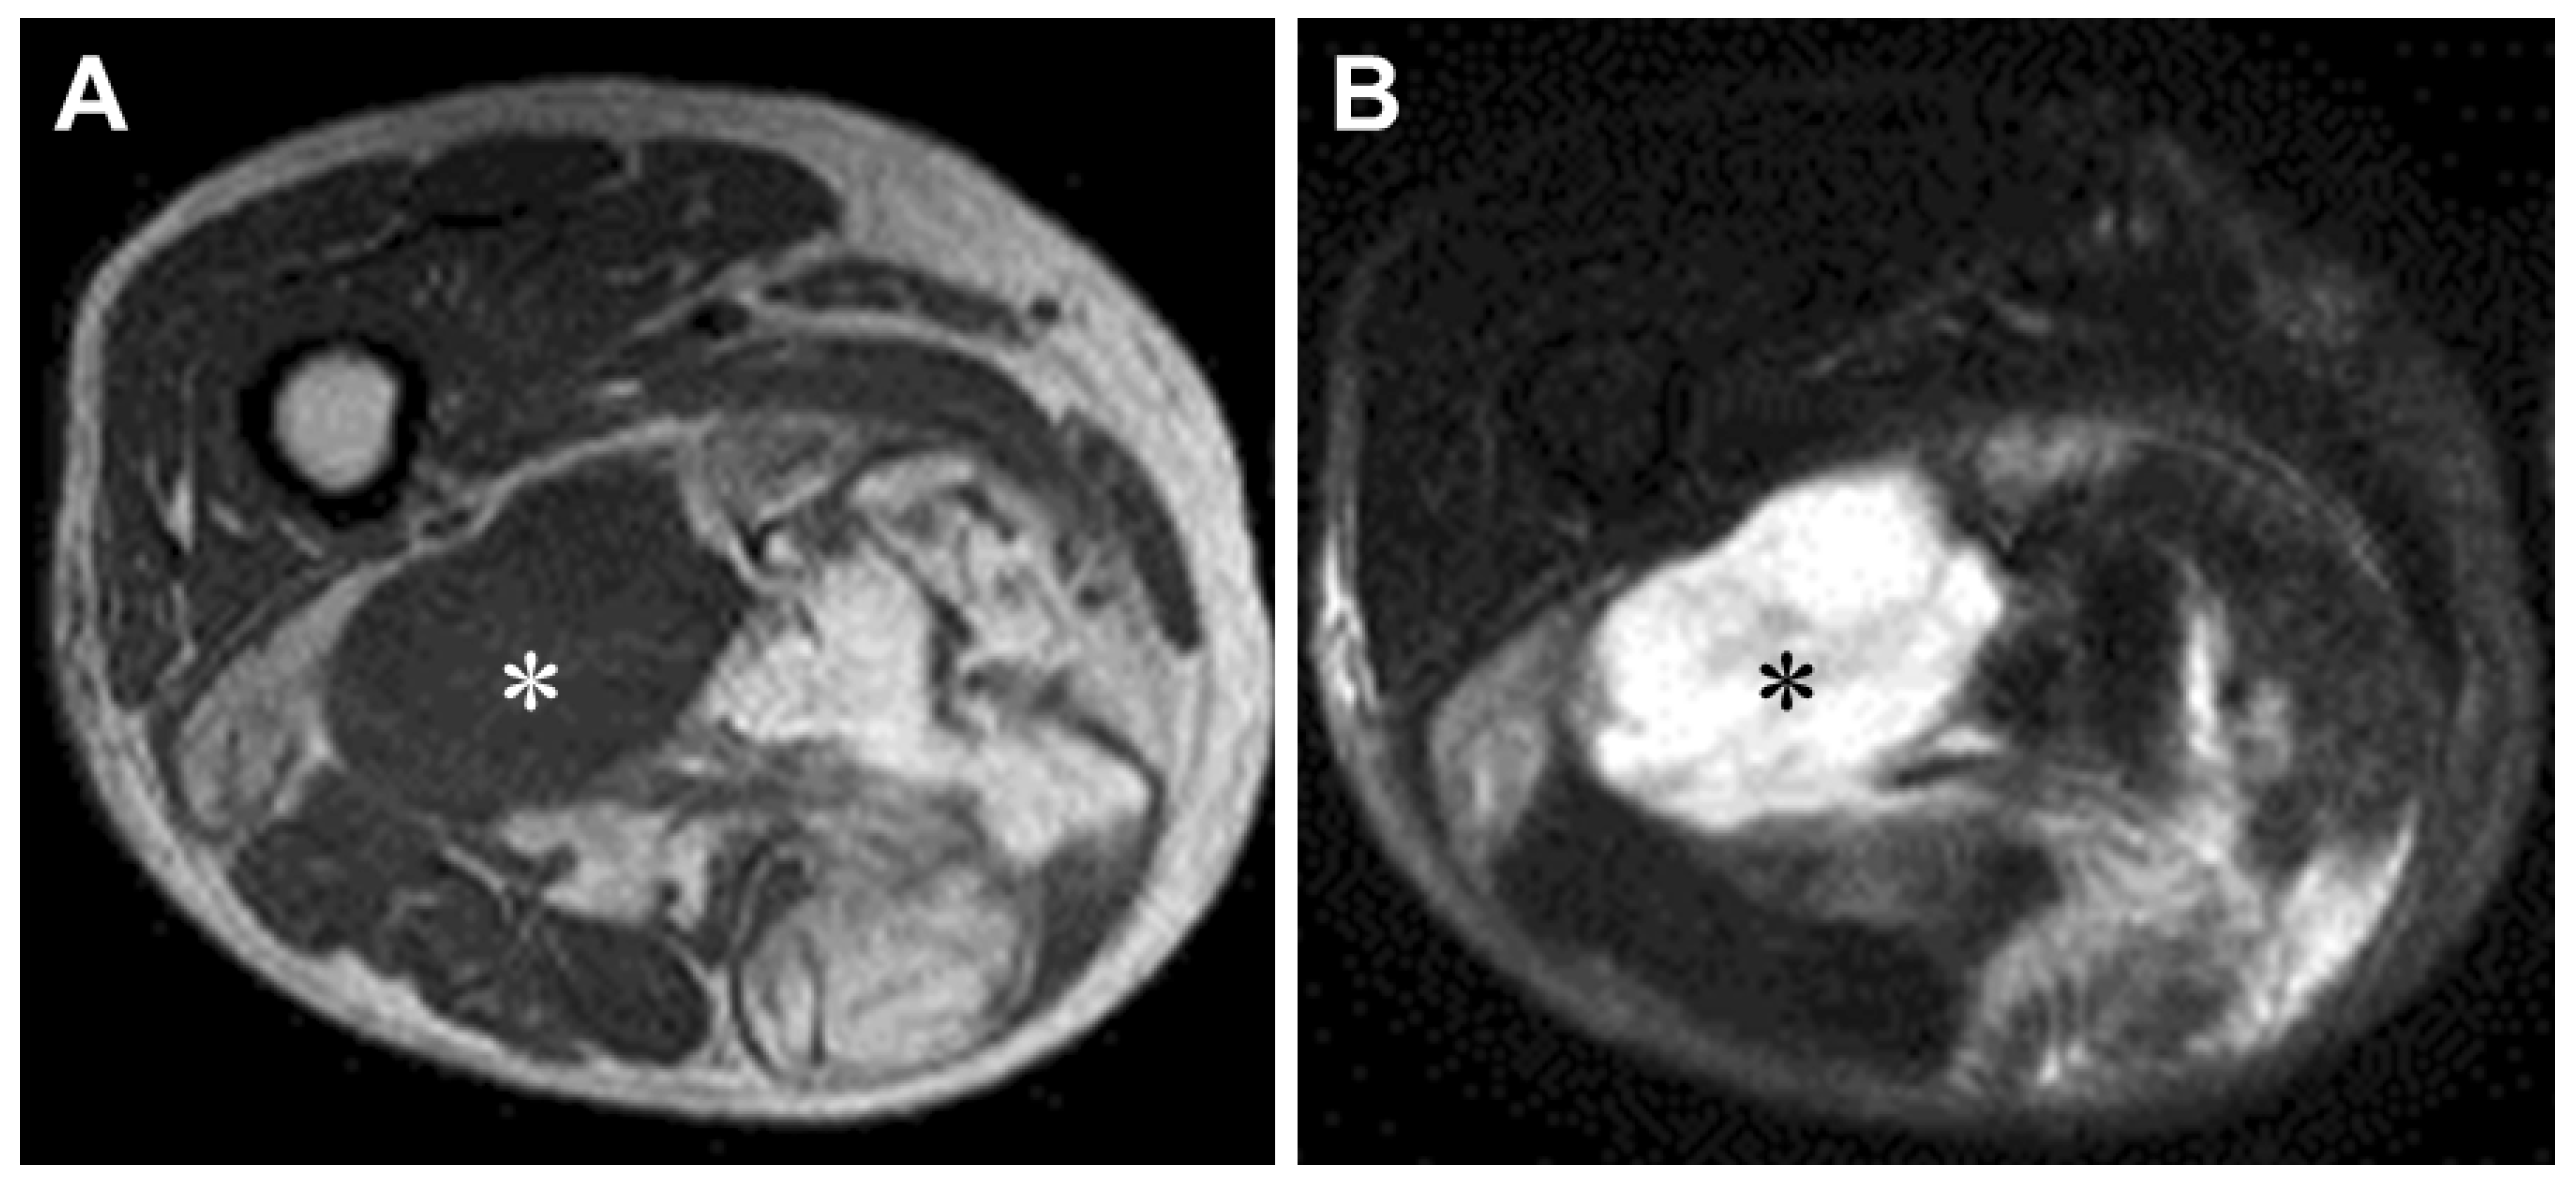

Magnetic resonance imaging (MRI) is the preferred modality for evaluating soft tissue lesions and is helpful in demonstrating the fatty nature of the tumor. DDL represents a biphasic neoplasm, with one component being a WDL/ALT and the other a non-lipogenic sarcoma (Figure 1). The WDL/ALT component demonstrates high signal intensity on both T1- and T2-weighted images, consistent with a lipomatous tumor. The dedifferentiated component is usually larger than 3 cm [10] and typically shows a non-specific MR appearance with prolonged T1 and T2 relaxation times. Hemorrhage and necrosis may be seen within the high-grade dedifferentiated component. In our limited experience, gadolinium contrast enhancement of the dedifferentiated component is variable.

Figure 1.

Magnetic resonance imaging of dedifferentiated liposarcoma in the right thigh of an 83-year-old woman. Axial T1-weighted (A) and T2-weighted spectral presaturation with inversion recovery (B) sequences display a large soft tissue mass composed of non-lipomatous (white and black asterisks) and juxtaposed lipomatous components.